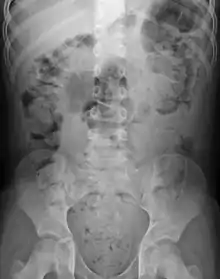

Significant constipation in the plain X-ray of an 8-year-old